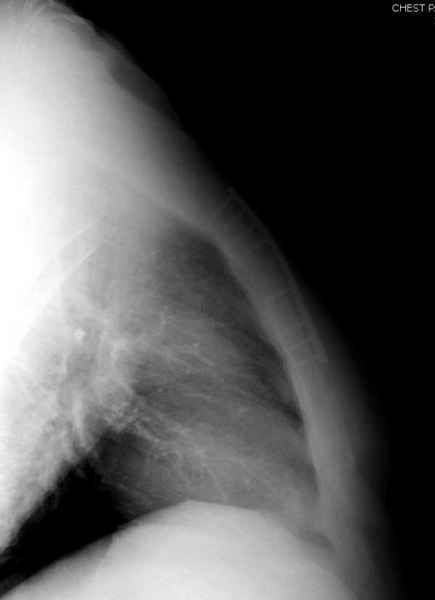

Юра, интересно, насколько такой остеосинтез контролирует степень репозиции, а то у меня имеются снимки девочки 11 лет, направленной ко мне на консультацию из одной из республик бывшего союза.

После торакальной операции, по-видимому, сильно натянули проволоку, и в результате получился захлест отломков в друг друга.

А простые посттравматические ложные суставы грудины приходилось оперировать с ограничителем сверла и с фиксацией 2.4 мм пластинами с угловой стабильностью.